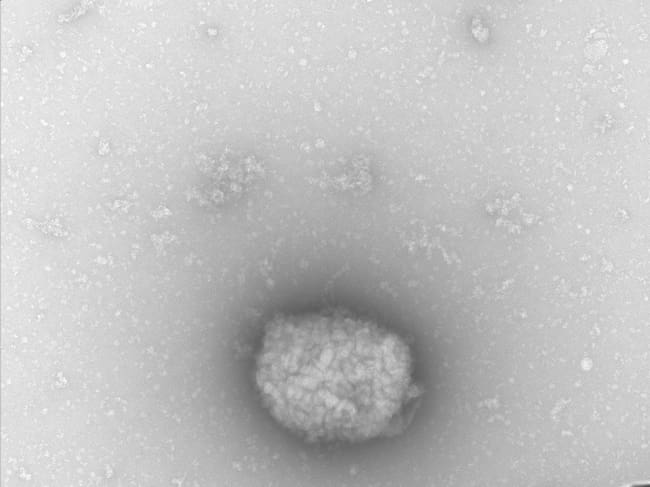

Partículas virales del virus del mono (monkeypox virus) observadas por microscopia electrónica de transmisión directamente del líquido obtenido de pústulas de pacientes infectados. / Milagros Guerra? Bruno Hernaez y Antonio Alcamí (EFE)